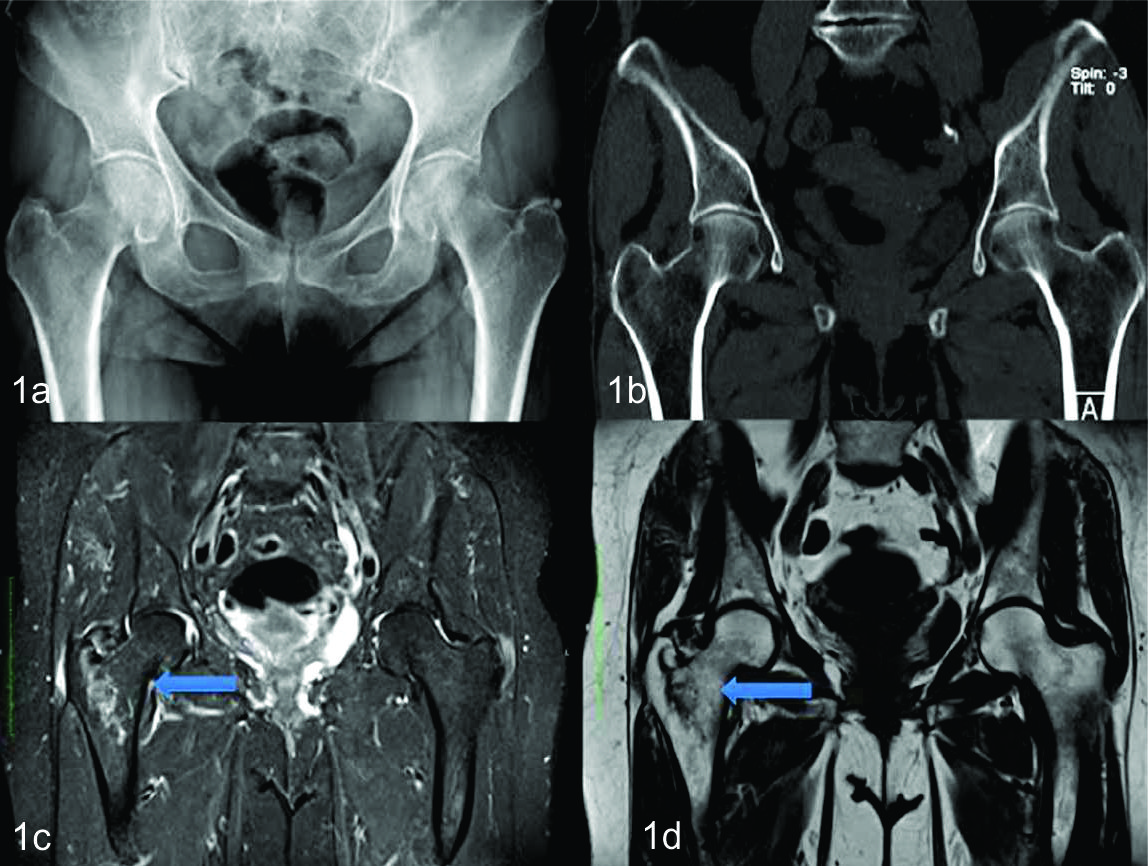

Figura 1

81 años sexo femenino.

a) Radiografía de pelvis frente- No se observan trazos de fractura. b) TC de pelvis, reconstrucción MPR en plano coronal. No se observan trazos de fractura en cuello femoral derecho. c) y d) RM de pelvis en plano coronal en secuencia STIR y TSET1 respectivamente. Se observa fractura intertrocantérica derecha (flechas).